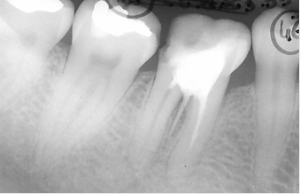

Reprise du traitement endodontique , séparation des racines et curetage inter-radiculaire.